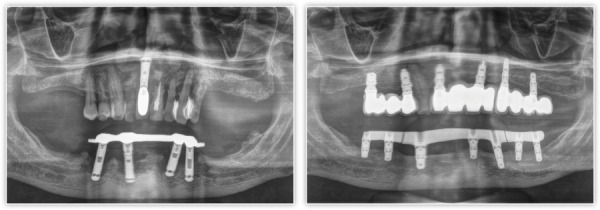

牙周病(PD)是一种世界范围内高发的口腔疾病。牙周病有不同的治疗方法,近年来的趋势是微创治疗。如果种植体不能长期治疗,我们也应该考虑使用非创伤性方法移除种植体并对该病例进行再治疗。在植入植牙体和在种植周炎后维持植牙体或更换植牙体时,需要考虑的一点是患者的牙周状况。在这种情况下,牙周病会影响我们治疗的预后。在以下的临床病例中,我们展示了一种微创方法治疗PD和种植周炎患者。

Periodontal disease (PD) is an oral pathology with a high prevalence worldwide. There are different treatments for periodontal disease, with the trend in recent years being towards minimally invasive treatments. In cases where implants cannot be treated predictably in the long term, we should also consider removing the implant using atraumatic methods and retreatment of the case. A point to be taken into account both for the insertion of a dental implant and for its maintenance after periimplantitis or for its replacement is the periodontal status of the patient. Periodontal disease can affect the prognosis of our treatment in this type of situation. In the following clinical case, we show the treatment of a patient affected by PD and periimplantitis with a minimally invasive approach.